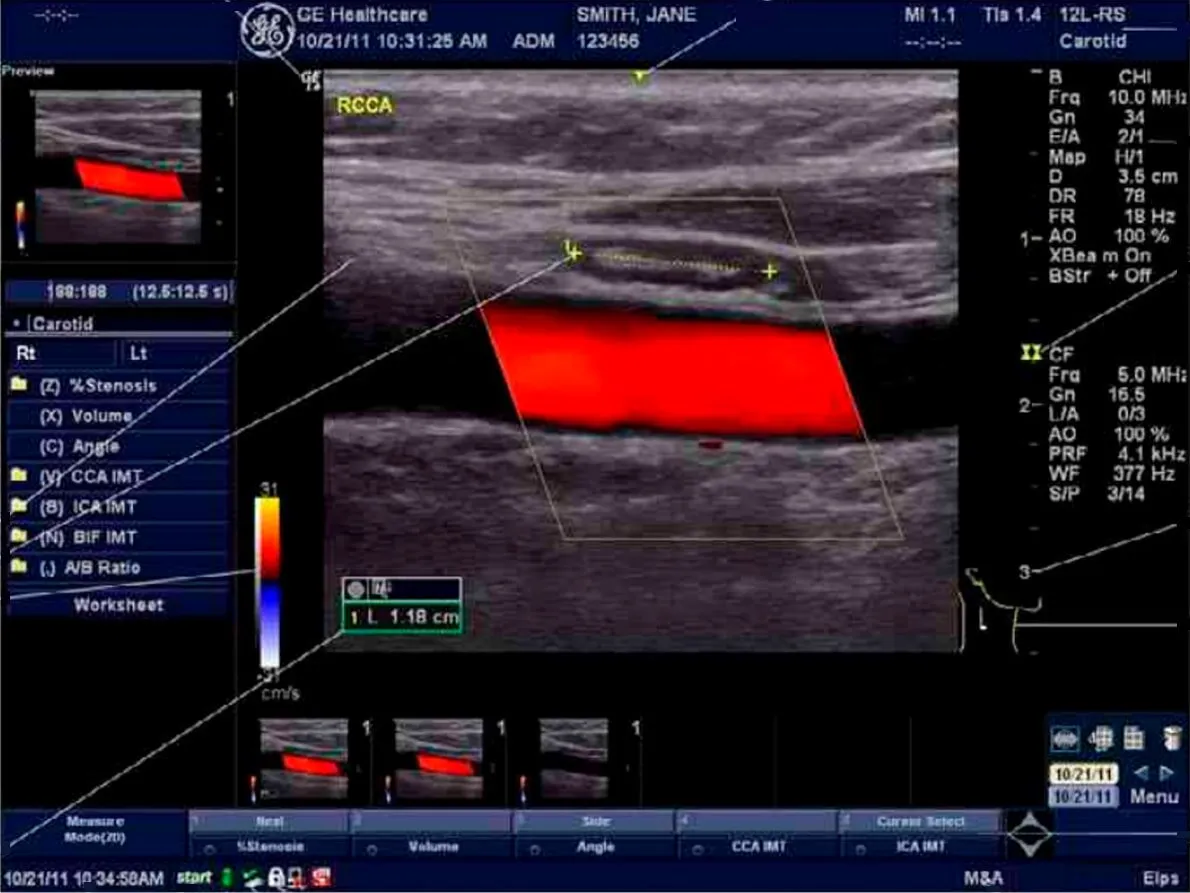

- Стандартные режимы сканирования: В-режим, М-режим, цветовое допплеровское картирование, энергетический допплер (включая направленный), импульсно-волновой допплер

- Стандартные режимы сканирования: В-режим, М-режим, цветовое допплеровское картирование, энергетический допплер (включая направленный), импульсно-волновой допплер

- Ангиология

- 9L-RS линейный датчик, широкополосный, мультичастотный с диапазоном частот 3,0-9,0 МГц. Клиническое применение: Периферические сосуды, сосудистый доступ, скелетно-мышечные.

- 12L-RS, линейный датчик, широкополосный, мультичастотный с диапазоном частот 4,2-13,0 МГц. Клиническое применение: периферические сосуды, поверхностно расположенные органы и структуры, скелетно-мышечные, нервные блокады, плевра, офтальмология и контроль иглы

Систему отличает наличие датчиков со сверхвысокими частотами сканирования, эталонная чувствительность доплеровских режимов для сосудистых исследований, в том числе наиболее сложных транскраниальных, а также высокая частота кадров, которая необходима для качественных кардиологических исследований.

- Программы сосудистых расчетов, кардиологических расчетов, расчетов для акушерства и гинекологии, урологии.

- Автоматическое оконтуривание спектра и обсчет более 10 параметров кровотока в реальном времени.